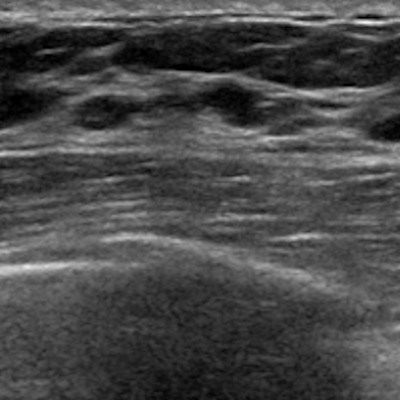

Conventional ultrasound of breast tissue (top) compared to the new method (bottom). Conventional ultrasound relies on the amplitude of signals, turning high and low signals into blacks, whites, and grays. The new method is “coherence-based,” meaning the image relies on how similar signals are to neighboring signals.Johns Hopkins University

Complicated cysts can appear on ultrasound like solid masses, which results in multiple unnecessary procedures or follow-up exams. When used on dense breasts, ultrasound waves can scatter before reaching masses, resulting in acoustic cluttering on images.

Bell and colleagues attempted to improve how ultrasound signals are processed with an approach that is “coherence-based.” This means that the image relies on how similar signals are to neighboring signals, resulting in a number score for each mass. The researchers hypothesized that this would make it easier for radiologists to find suspicious masses on ultrasound.